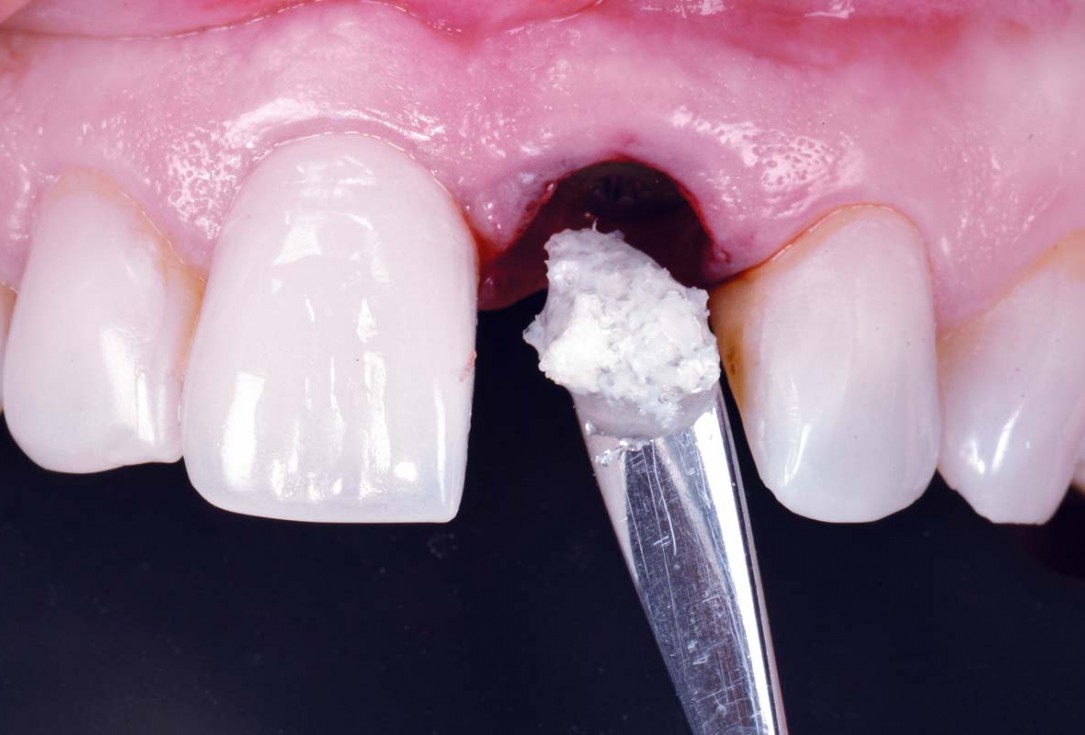

19/30 - Filling the gap with maxgraftExcellent aesthetic result of buccal augmentation with mucoderm® and maxgraft® after immediate implant placement - 3-years follow-up - Dr. A. Puišys

21/30 - Gap filled with maxgraftExcellent aesthetic result of buccal augmentation with mucoderm® and maxgraft® after immediate implant placement - 3-years follow-up - Dr. A. Puišys